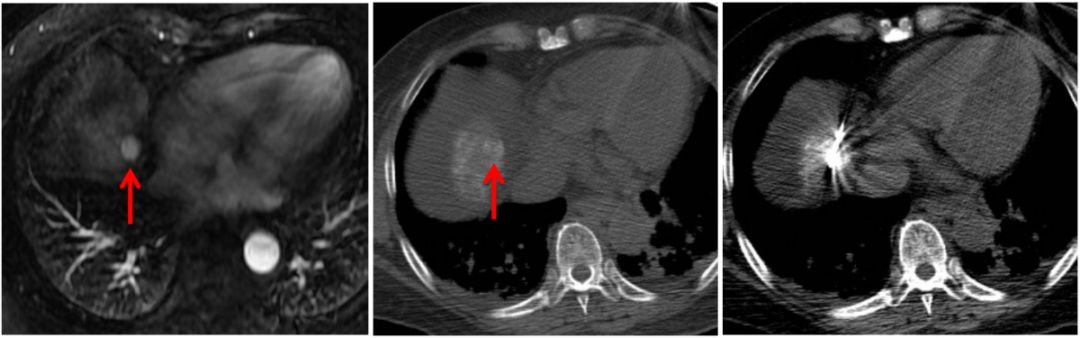

由于肝脏特殊的生理解剖,临近危险器官的特殊部位以及影像显示不清的肝肿瘤,一直是影像引导下经皮消融治疗的难点或“禁区”。 近日,我院放射科介入病房邵海波教授、田玉龙主治医等在麻醉科的大力配合下,为一名复杂的肝癌患者进行了影像引导下的经皮微波消融治疗。手术仅历时1.5小时,术后3天患者即顺利出院。 患者为62岁女性,半年前诊断为原发性肝癌,为肝左叶单发病灶,曾行经导管肝动脉化疗栓塞和微波消融治疗,术后病灶完全灭活。本次入院MRI检查发现新发肿瘤,肝内共有4个活性病灶,分别位于心缘旁、膈顶、胆囊旁等“危险部位”,血供较差,TACE治疗控制不佳,经详细讨论,决定采用经皮微波消融治疗。由于病变位置特殊,加之平扫CT或超声均不能清晰的显示全部病灶,大大增加了消融治疗的难度和风险。术中,治疗团队采用腹水隔离、CT/超声双引导进针监测、解剖标记定位、低功率间断消融等多种辅助手段相结合,对全部4处病灶进行了安全、精准的微波消融治疗,手术历时1.5小时,术后3天患者顺利出院。 图1. 临近心脏的膈顶部病灶,水隔离保护下消融 图2. 临近包膜的膈顶部病灶,水隔离保护消融 图3. 紧邻胆囊病灶,超声引导和监测下低功率间断消融 图4. CT和超声均显示不清的病灶,采用CT引导解剖标记定位消融 图5.肿瘤消融治疗是指利用消融治疗针穿刺肝肿瘤,针尖能够产生电磁波而使周围组织升温至80度以上的高温,从而杀灭肿瘤。 图6.危险部位肿瘤是指当肿瘤靠近膈顶、心脏、胃、肠管、胆囊、以及肝门部等部位时,对肿瘤进行消融就容易损伤相应的器官,引起并发症。因此这些部位的肿瘤称为危险部位肿瘤。 此病例癌症病灶位于膈顶部、心脏旁、胆囊旁、肝门部、大血管附近,肝边缘近胃肠道、外凸近腹壁,治疗难度大,技术复杂、成功率低、风险高。介入病房开展水隔离技术、胆管冷却技术、术中引流技术、造影增强定位技术、解剖标记定位技术、复合影像导航穿刺和监视技术等新技术对危险部位和复杂病灶进行成功的经皮消融治疗,几乎做到肝脏肿瘤消融无禁区、无死角。 近年来,影像引导下经皮微波消融治疗已成为肝癌/肝转移癌、肺癌、肾癌等实体肿瘤最为有效的微创治疗手段之一,具有创伤小、恢复快、疗效确切、可重复治疗等优点。据统计,2018年,放射科介入病房利用各种辅助技术处理复杂或高危部位肿瘤41例,疗效显著且无并发症发生,与前期未应用辅助技术的病例相比,完全消融的比率显著提高(93.5% vs.78.5%),不良反应发生率显著降低。 我院放射科介入病房自2004年开始开展影像引导下肝癌的射频/微波消融治疗,在放射科副主任苏洪英教授的领导下,不断突破技术难点,治疗水平逐年提高。科室选派技术骨干到国外学习先进技术,其中本例手术的术者邵海波教授就是在我院中青年骨干培训计划的支持下,在哈佛医学院/麻省总医院进行了为期近2年的消融治疗培训和研究后,回国将所学更好地应用于临床。目前,科室在影像引导下经皮肝肿瘤微波消融领域处于国内领先水平。